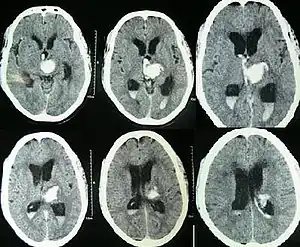

![]() | |

| CT scan of a spontaneous intracerebral bleed, leaking into the lateral ventricles | |